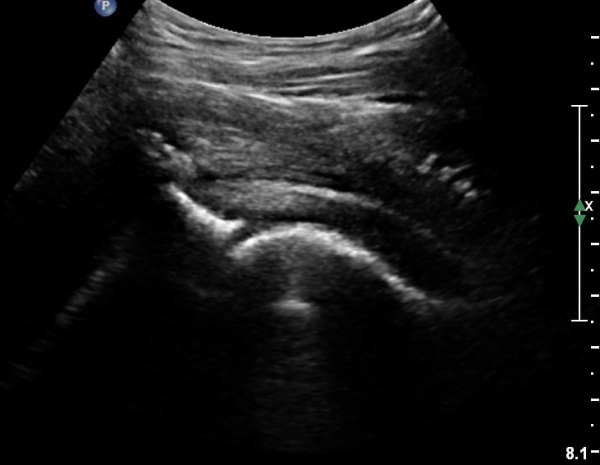

[¾ûµ¢ÀÌ] °í°üÀý Ãæµ¹ÁõÈıº¿¡ÀÇÇÑ È°¾×¸·¿° ÁÖ»çÄ¡·á